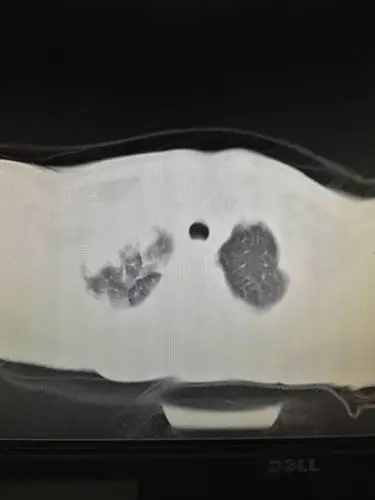

我这样有一段时间了,我怕自己得了什么病,他们说是肺结核,我都快吓死

两周前拍ct得出局限性支扩(湿扩吧)我之前咳唆咳痰(得过肺结核见局限

虫蚀空洞结核(哈尔滨胸科医院王秀峰老师)